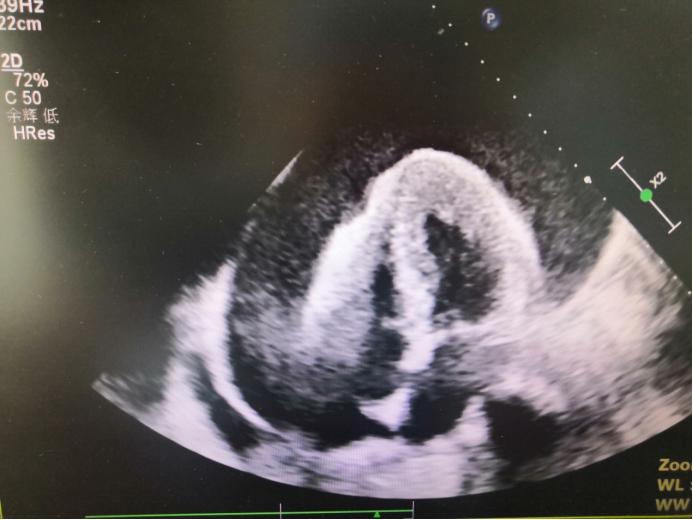

不幸的是,4天前小凯感冒后出现气短胸闷,一经检查,发现正在减少的心包积液又在快速增长,可怕的是,随着心包积液的增长,心脏就像一个钟摆一样在心包内摆动,这对于心脏射血来说影响极大。很快,小凯出现气短加重、口唇紫绀、血压低、四肢冰冷等梗阻性休克表现,由肾病科紧急转入重症医学科治疗。

超声下摇摆的心脏